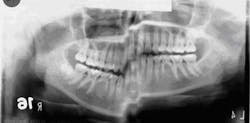

X-ray answerThe imaging error was caused by patient movement during exposure; note the step defect in the inferior border mandible. Film exposing and handling tips

- If portions of a panoramic radiograph are blurred and exhibit large steps as seen with the inferior border mandible, the X-ray may need to be retaken.